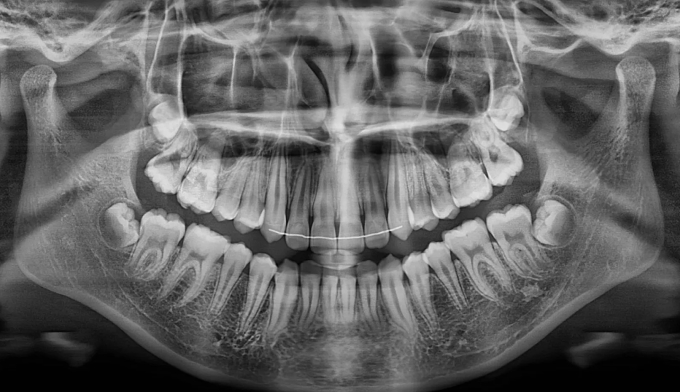

송곳니가 나올 공간이 전혀 없어 보입니다.(화살표로 표시한 부분이 송곳니가 나와야 할 공간입니다)

치아교정은 바른 교합을 형성하는것이 중요한 목적이기 때문에 윗니와 아랫니를 모두 교정하는것이 올바른 방법이지만, 특수한 경우에 있어서는 한쪽만 교정을 진행하는 경우도 있습니다.

위와 같은 경우는 환자 개인적인 사정으로 윗니만 교정한 경우입니다.

안모를 고려하여 앞니가 앞으로 뻗치지 않게 주의하면서 어금니만 후방이동시켜 송곳니가 맹출할 공간을 만듭니다.

총 교정기간은 13개월이 소요되었습니다.